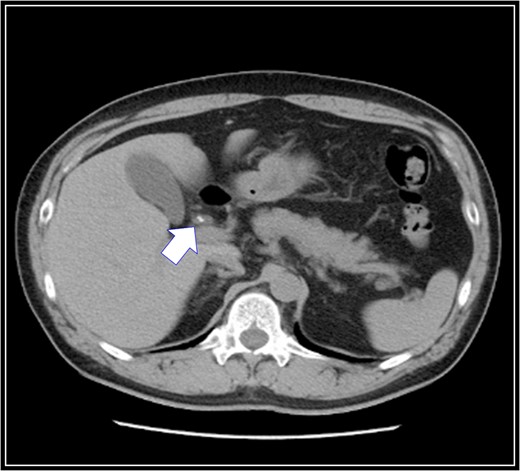

The patient was placed in supine position. Initially, intracorporeal procedures were performed in the laparoscopic view through four trocars (one 12-mm port and three 5-mm ports). We considered using intraoperative cholangiography to explore the right accessory hepatic duct. We incised the serosa by the neck of the gallbladder, used the Rouviere sulcus as a landmark, and peeled off the Calot triangle near the gallbladder. Subsequently, we identified the cystic artery and isolated it. Then we identified the cystic duct, and we inserted a cholangiography tube into it. The intraoperative cholangiography image showed that the right accessory hepatic duct branching from the cystic duct dominated an anterior segment of the right hepatic lobe (Fig. 3). Next, we isolated the cystic duct while preserving the right accessory hepatic duct. We resected the gallbladder. The total operating time was 125 min, and the intraoperative blood loss was minimal. Since the patient's postoperative course was uneventful, he was discharged 4 days later. We performed drip-infusion cholangiography-CT (DIC-CT) 48 days postoperatively. The DIC-CT scan demonstrated that the right accessory hepatic duct was intact, and it dominated an anterior segment of the right hepatic lobe (Fig. 4).

Intraoperative cholangiography image. The right accessory hepatic duct branching from the cystic duct (white arrow) dominates an anterior segment of the right hepatic lobe.